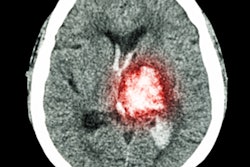

Lesser cortical thickness is a marker of degeneration of brain health and risk of Alzheimer's, while higher white-matter hyperintensity volume is associated with small-vessel cerebrovascular disease and thus risk of stroke, cognitive decline, Alzheimer's disease, and rate of Alzheimer's progression. Previous studies have found poorer brain health in Black, Indigenous, and people of color (BIPOC) individuals in later life compared with their white counterparts, but more research is needed to determine the quality of brain health in this population at midlife, Turney's team wrote.

- Racial and ethnic differences in cerebrovascular disease appeared in both midlife and late life, while disparities in cortical thickness appeared only in late life.

- Black-white disparities for both cerebrovascular disease and cortical thickness were greater than Latinx-white disparities, and Black-Latinx differences for these measures were slight.

- Brain aging was greater at midlife in Black individuals compared to their Latinx and white counterparts.